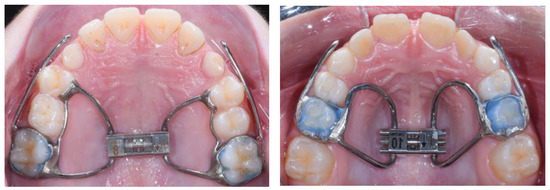

2.4.1. Center #1

2.4.2. Center #2

2.4.3. Center #3